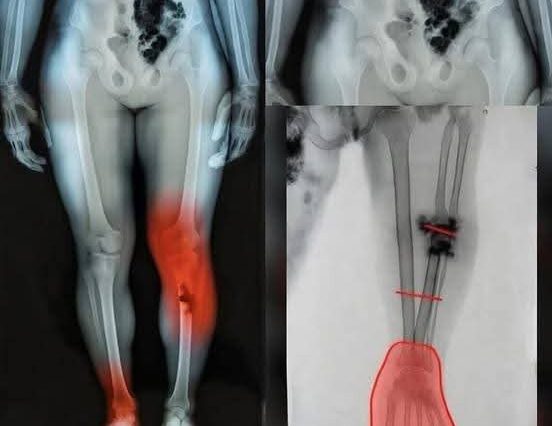

El sorprendente caso de Tomm Tennent: el bebé que desconcertó a la medicina y desafió todos los pronósticos